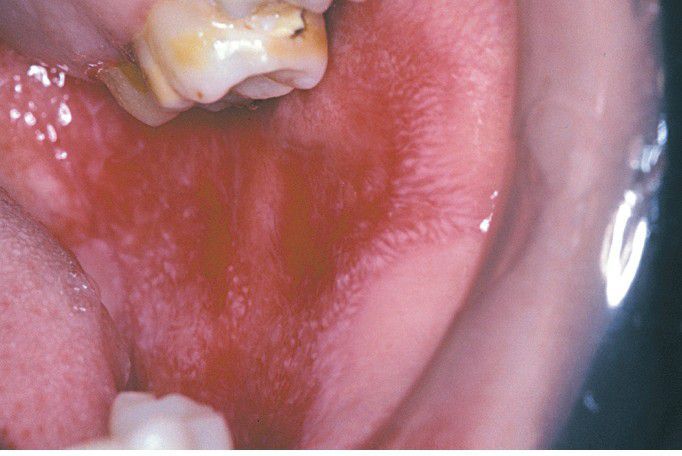

Chronic Cutaneous Lupus Erythematosus (CCLE).

Radiating keratotic striae surround erythematous zones of the buccal mucosa. These features are similar to those of erosive lichen planus.